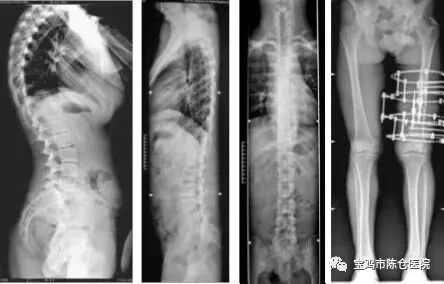

5.长骨拼接功能:长骨拼接技术具备高速和低剂量的特点,图像采集仅需18-25秒即可完成图像拍摄,同时剂量仅为四次DR拍摄的剂量。

一机多用

该设备既可以完成消化道造影、静脉肾盂造影等各种造影检查,并可做头颅、脊柱、胸腹部及肩、髋、膝关节等全身各部位的数字化X线摄片,四肢全长及脊柱全长摄影;数字胃肠的检查床可以左右上下移动,可减少骨折等病人的移动。